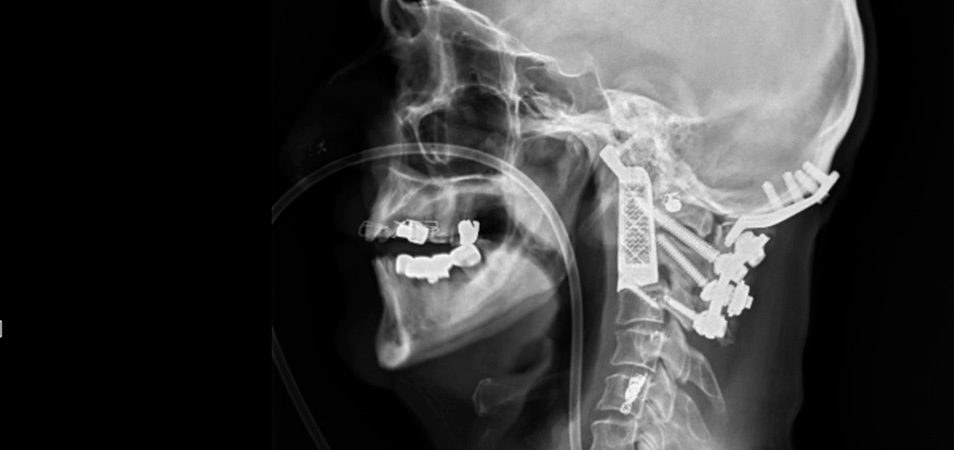

Eso es lo que ha ocurrido en Sídney, Australia, donde el neurocirujano Ralph Mobbs ha utilizado la impresión 3D para eliminar un tumor en la base del cráneo de un paciente de 60 años y sustituir las dos vértebras a las que había afectado, de otro modo el avance del cáncer le habría dejado sin movilidad.

No es la primera vez que se reconstruyen vértebras utilizando hueso del paciente, pero Mobbs decidió innovar y probar con la impresión 3D para lograr un mejor resultado.

Trabajó en conjunto con la empresa Anatomics, que no sólo se encargaron de imprimir en titanio el implante de las vértebras, sino que también crearon por impresión 3D varios modelos de la anatomía de la zona exactamente como la del paciente. ¿Para qué? de esta forma el neurocirujano podría ensayar la operación.